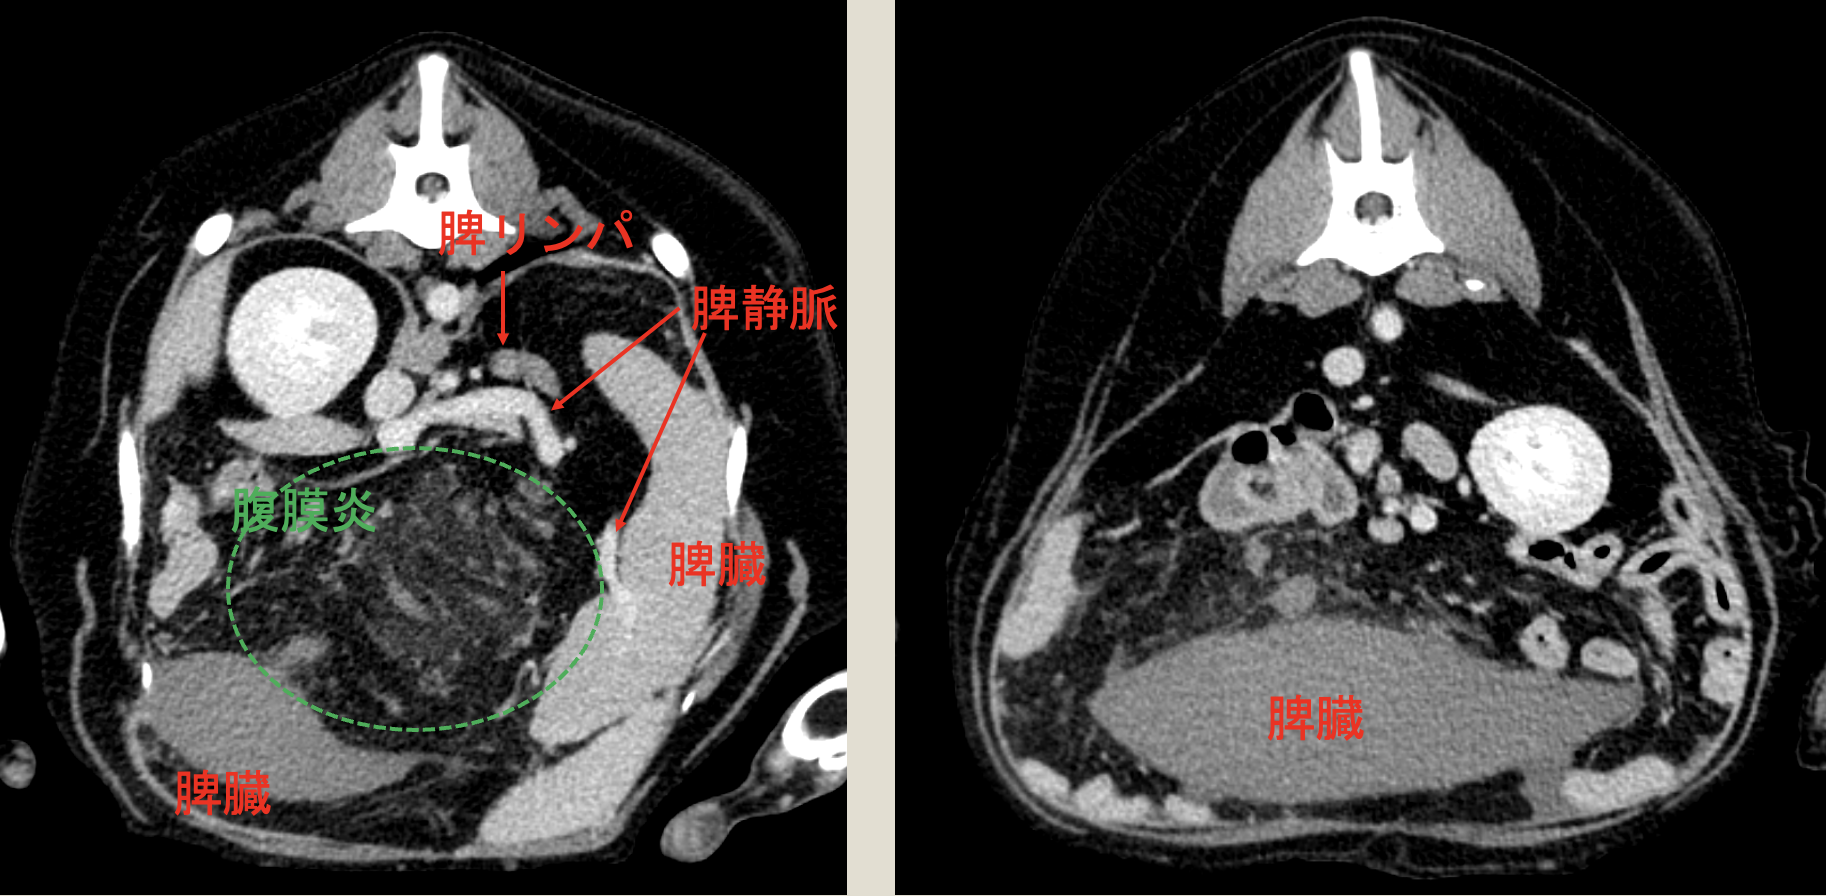

CT検査より、脾臓以外に血流に乏しい腫瘤、腹膜炎

脾臓捻転・脾臓断裂を疑い、開腹にて腫瘤摘出